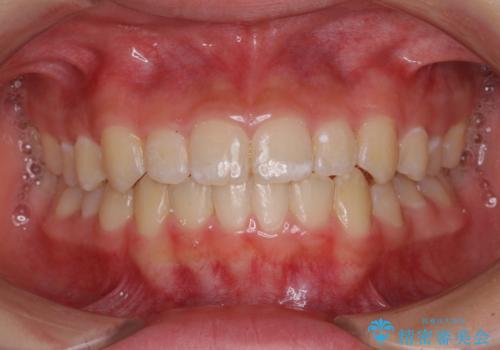

上下の骨幅を改善したことで、スムーズに歯列矯正を行うことができました。

インビザライン治療開始直後に遠方に引っ越しをされたため、通院間隔が長くなり、治療期間が長くなりましたが、しっかりと治療を行うことができました。